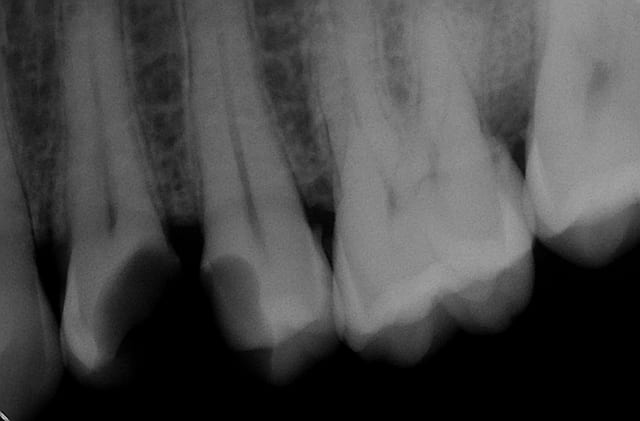

Alors comment traiteriez vous cette 24 asymptotique, qui présente un enorme délabrement sous gingival , notez que l'émail n'est plus soutenu par la dentine à aucun endroit ?

1ère séance remontées de la marche distale au compo flow + compo de restauration / réalisation d'un IDS , le tout sous digue bien sur (voir radio jointe , désolé à l'envers))

Voici les photos toutes fraiches de ce matin.

Vos critiques sont bien sur les bienvenues je dois encore beaucoup m'améliorer sur les prises de teintes, et je m'y attelle en ce moment,, par contre en ce qui concerne la pérennité de la restauration…..ma patiente a sa dent bien vivante, aucun joint sous gingival , possibilité de réaliser une endo dans le futur sans détruire la restauration existante si besoin, possibilité re refaire un onlay dans quelques années si ça casse, toujours sur dent vivante…. bref la liste des avantages est très longue par rapport au classique endo-IC-CCM.